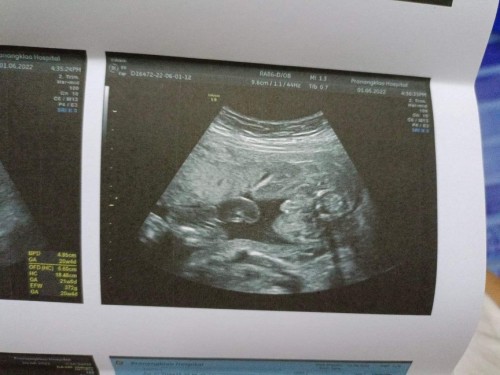

ตอนนี้ท้องได้22w แล้วค่ะ ซาวด์ตอน20w หมอบอกน้องเพศชาย 90% แม่ๆว่า ภาพนี้เห็นจู๋น้องชัดไหมค่ะ ☺️👶#ขอคำแนะนำหน่อยค่ะ

ดูไปดูมาเหมือนสายสะดือไหมคะแต่คุณหมอบอกว่าผู้ชาย🤣🤣🤣น่าจะชายจริงๆ😅

จู๋จ้า ถ้าลูกสาวจะเรียบเลย

มองไม่ชัดอะค่ะ แต่เรียบนะ

ซาวด์ตอน21wค่ะมาชัดเลย

ชัดเเจ๋วเลยคร่าาาา